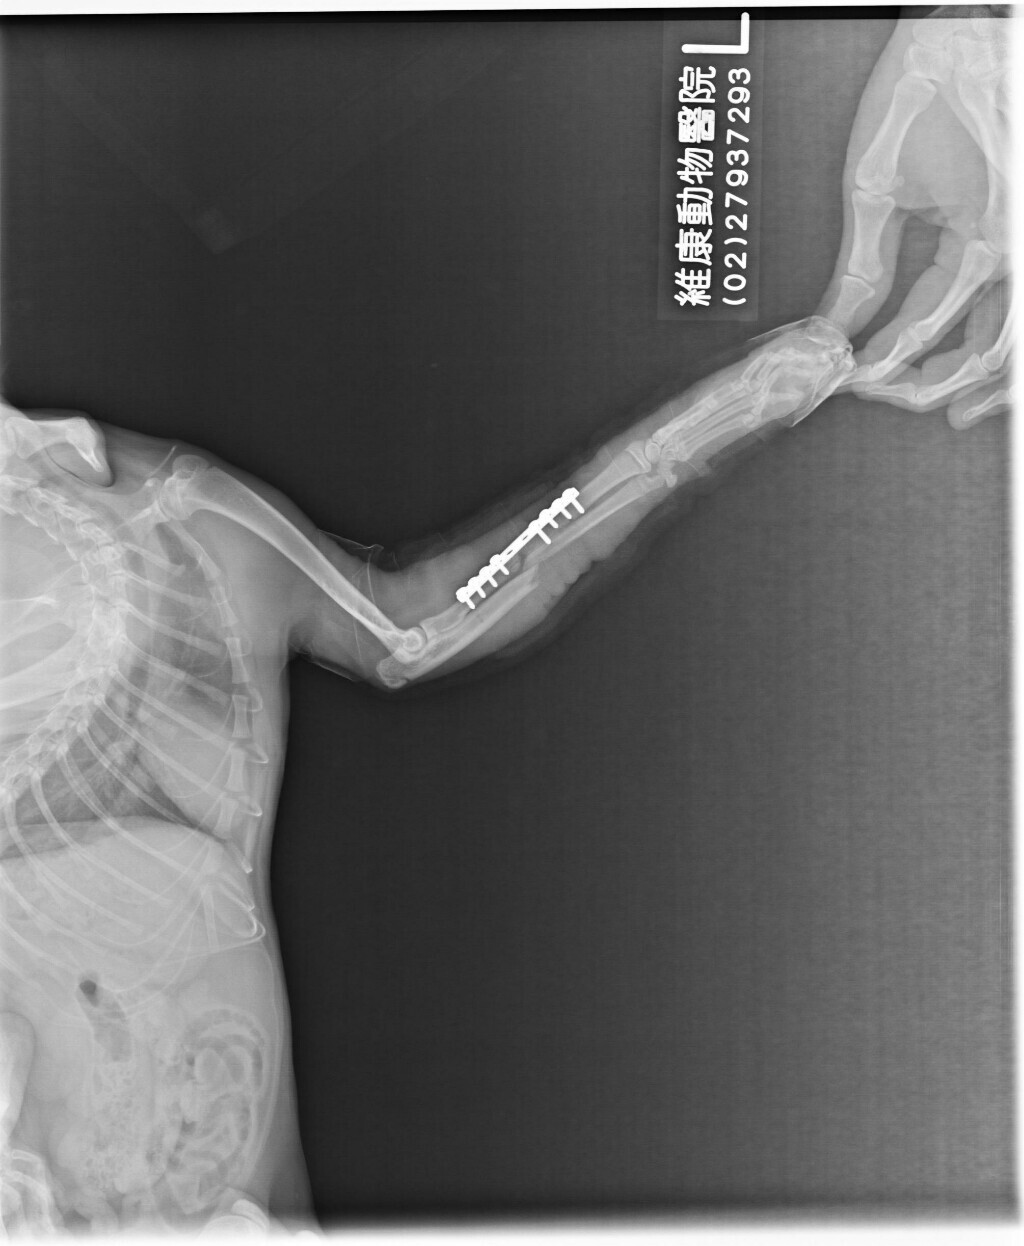

主題: 骨折脫臼的弟弟 申請者姓名: 潘鑫沛 花色: 申請日期: 2017-07-12 19:13:32 申請者部落格: 申請者臉書網址: https://www.facebook.com/profile.php?id=100000369575090 所在縣市/合作醫院: 台北市/內湖維康動物醫院 治療費用: 32620元 需求人數: 35人 已結案 (2024-06-01 13:25:41) 報名人員: 丁小乖(已付款)、Aisha Lung(已付款)、丸子 x2(已付款)、潘小潘 x6(已付款)、chris(已付款)、薇薇安(已付款)、王員外的爹(已付款)、徐雅嬪(已付款)、小爵貓 x2(已付款)、tigercat(已付款)、Cian Huei Yang、Cian Huei Yang(已付款)、Kuo Wei(已付款)、claire(已付款)、貓步小姐-美鞋專賣(已付款)、Juen-Nien Lin(已付款)、lunyi(已付款)、林雅雯(已付款)、長春路四面佛(已付款)、evelyn.lin66 x9(已付款)、李庭芝(已付款)、 候補人員: 動物病情說明: 弟弟是我從小到大跟媽媽一起每天固定餵養的孩子,不常接觸陌生人,生活在無人走動的暗巷,隨著年紀越大好奇心越強,常常就跟著大孩子們走出巷子遊玩,缺少警戒心的他失蹤二天之後再出現時發現他走路左前腳跛腳無法著地以及臉部下顎腫脹,緊急將弟弟送醫,感謝TNR協會幫忙協助就醫事宜,不能確定到底為何受傷,只知道當找到孩子時,孩子大聲求救的叫聲是如此讓人心痛…孩子天生就很親人,當找到他時,眼神露出恐懼,一直往深處躲,哄了好久才把他哄出來,不敢想才10個月大的他到底在這不友善的地方遭遇了什麼事,讓他連我都害怕…孩子目前已轉院至維康動物醫院做內固定手術…目前弟弟醫療狀況:

1.左側橈尺骨複雜性骨折

2.左側腕部關節輕微鬆弛

3.左側下顎骨骨折

弟弟目前已完成手術,在醫院觀察2星期(6�13∼6�28)左右,醫師觀察他恢復良好,可接回家中安置休養,需關籠限制活動,避免激烈活動造成骨板斷裂,約2星期回診一次檢查骨頭復原程度…動物近況說明: 已接回家中安置中途,07�12回診,醫師表示斷骨部位的骨頭已漸漸長出新骨,恢復狀況良好,繼續關籠休養直到復原為止…下次回診日為08�02…